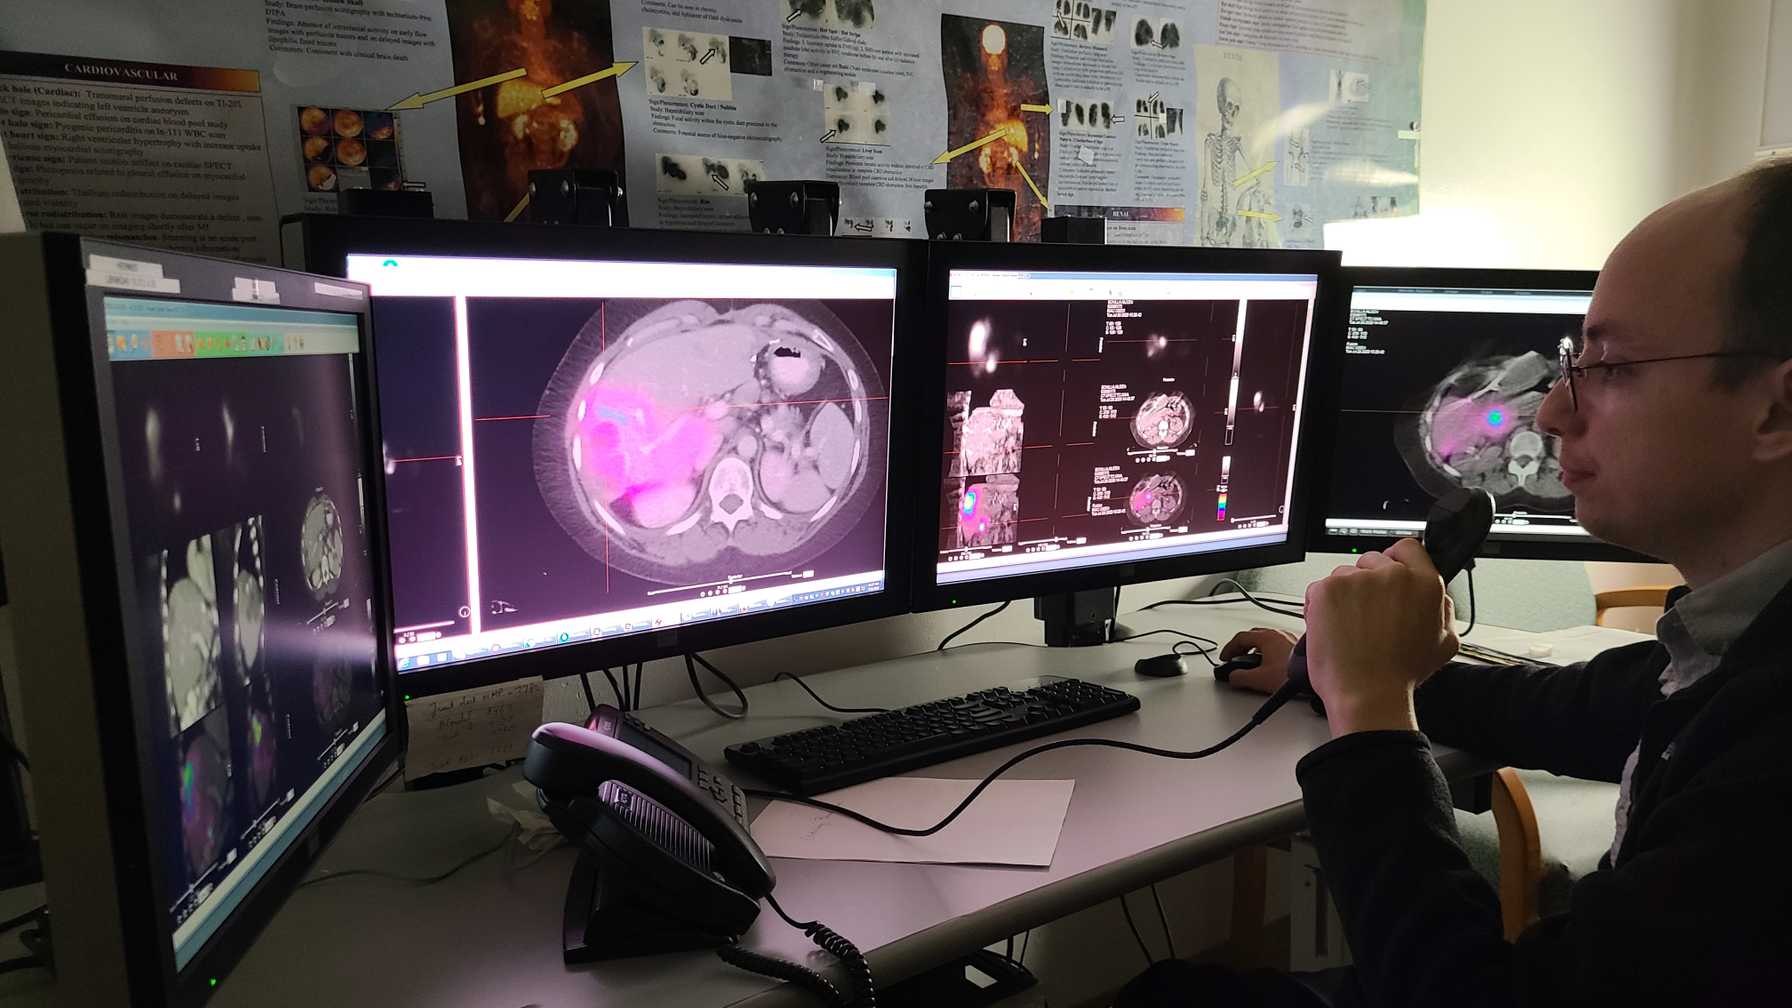

Nuclear Medicine Residency Program Virtual Tour

A pioneering program in its category, Montefiore Einstein’s Nuclear Medicine Residency Program is nationally and internationally recognized for its leading research in developing radioimmunotherapies. We offer a rich educational experience in which our trainees learn to manage a diverse array of clinical presentations using a wide range of diagnostic and therapeutic procedures.

Moses Campus, along with Children’s Hospital at Montefiore Einstein, features 726 adult inpatient beds and 106 pediatric inpatient beds. The facility also offers services to outpatients. As an NCI-Designated Cancer Center, Moses provides diagnostic and therapeutic modalities through an active theranostics program. While training at Moses, residents partake in a particularly rigorous program in oncologic and non-oncologic pediatric and adult nuclear medicine. Our Transplant Center, also on-site, affords residents the ability to evaluate organ physiology pre- and post-transplant.

Our 431-bed Jack D. Weiler Hospital is located adjacent to the Albert Einstein College of Medicine in the Morris Park section of the Bronx. While at Weiler, residents participate in independent, hands-on training, with a particular focus on emergency cases and nuclear cardiology studies overseen by an attending. Residents are also exposed to much of their on-call experience at this location.

An unmatched diversity of experience